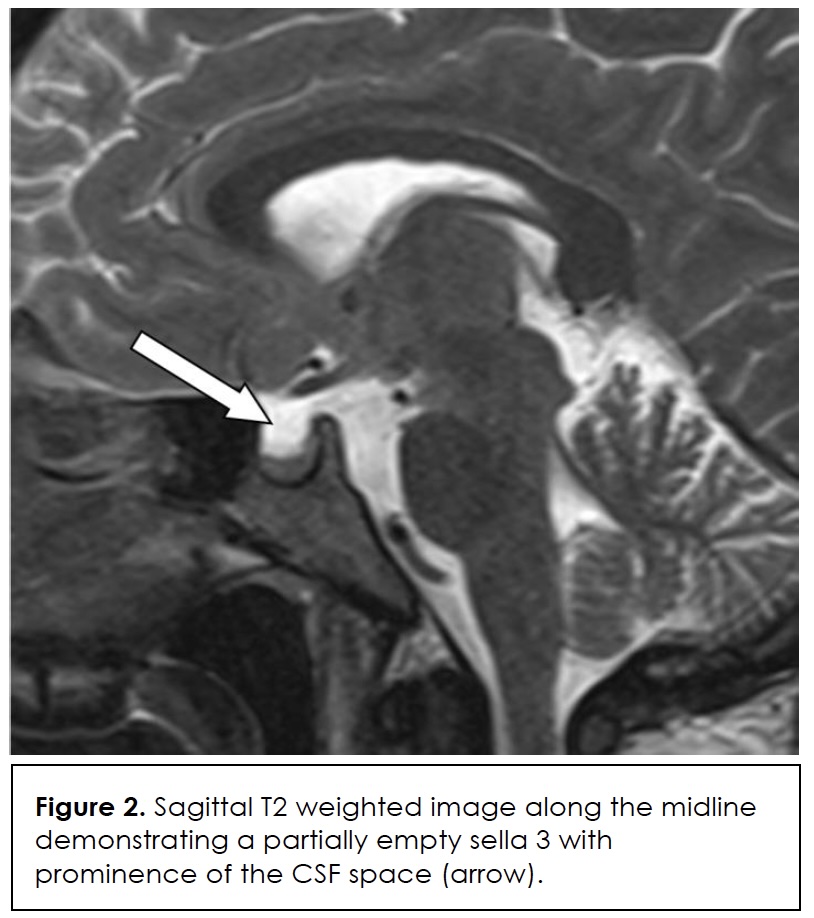

In this case, diagnostic specificity was also undermined by the patient’s simultaneous risk factors for infection and immunosuppression such as type 2 diabetes, obesity, recent adrenalectomy, and corticosteroid therapy. Her migraine history and probable idiopathic intracranial hypertension without papilledema (IIHWOP) initially predisposed towards a primary headache diagnosis. Brain imaging ruled out an intracranial mass, and she met two radiographic criteria for IIHWOP – empty sella (Figure 2) and transverse sinus narrowing (Figure 3) – that are consistent with the modified Friedman criteria for diagnosis 8. However, inability to demonstrate papilledema and absence of a persistent response to therapy prompted further investigation.